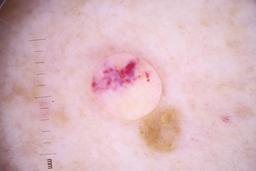

- Name: Challenge 2020: Training

- Number of images: 33,126

- Number of specified lesions: 32,701

- Number of specified patients: 2,056